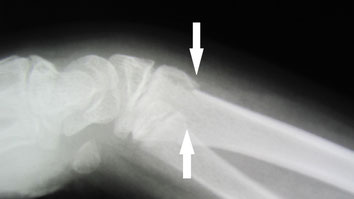

〇右前腕骨骨折(スミス骨折)

自転車で転倒し手をつき手首を骨折しました。

病院でレントゲン検査の結果、3か所の骨折が認められました。

後日手術の予定が組まれ,全身麻酔下で行うことを聞かされた時に非常に困惑し、セカンドオピニオンとして手の専門外科に相談に行かれました。

ここでも手術療法が妥当だと日程を組むことになってしまいました。

手術をしないで治ることはできないかとインターネットで調べ当院を知り相談に来られました。

骨折により保存治療が出る場合と手術療法が必須の場合があります。

しかし最近では一般的な骨折(転倒などにより起きる定型的な骨折)でも積極的に手術を勧められるケースが多くなってきています。特に総合病院では手術の傾向があるように思われます。

確かに骨折部位をプレートとビスにより内固定すれば強固な固定ができますが、患者さんのリスクとQOLの低下はどのようなところにあるでしょうか? 細かな説明がなく術後の経過観察はレントゲン検査の結果のみで評価し、日常の問題をよく聞いてもらえません。リハビリは理学療法士に任せ、術後の処置は看護師の役割になっています。

今回事情を聴き、整形外科の先生と相談をし当院で処置と経過観察をすることになりました。

整骨院の従来の固定法である副木(シャーレ)と包帯を駆使して患者さんに負担の少ない固定をしました。

毎日 固定具を外し患部の浮腫の除去、血行維持、清拭、超音波治療を行います。固定具に不自由があれば

修正をしました。 このように毎日患者さんに触れ、不安を聞くことにより自律神経も安定し良い結果につながるのです。

経過は非常に良好で転移(骨のずれ)もなく約2か月で薬剤師の仕事に復帰されました。